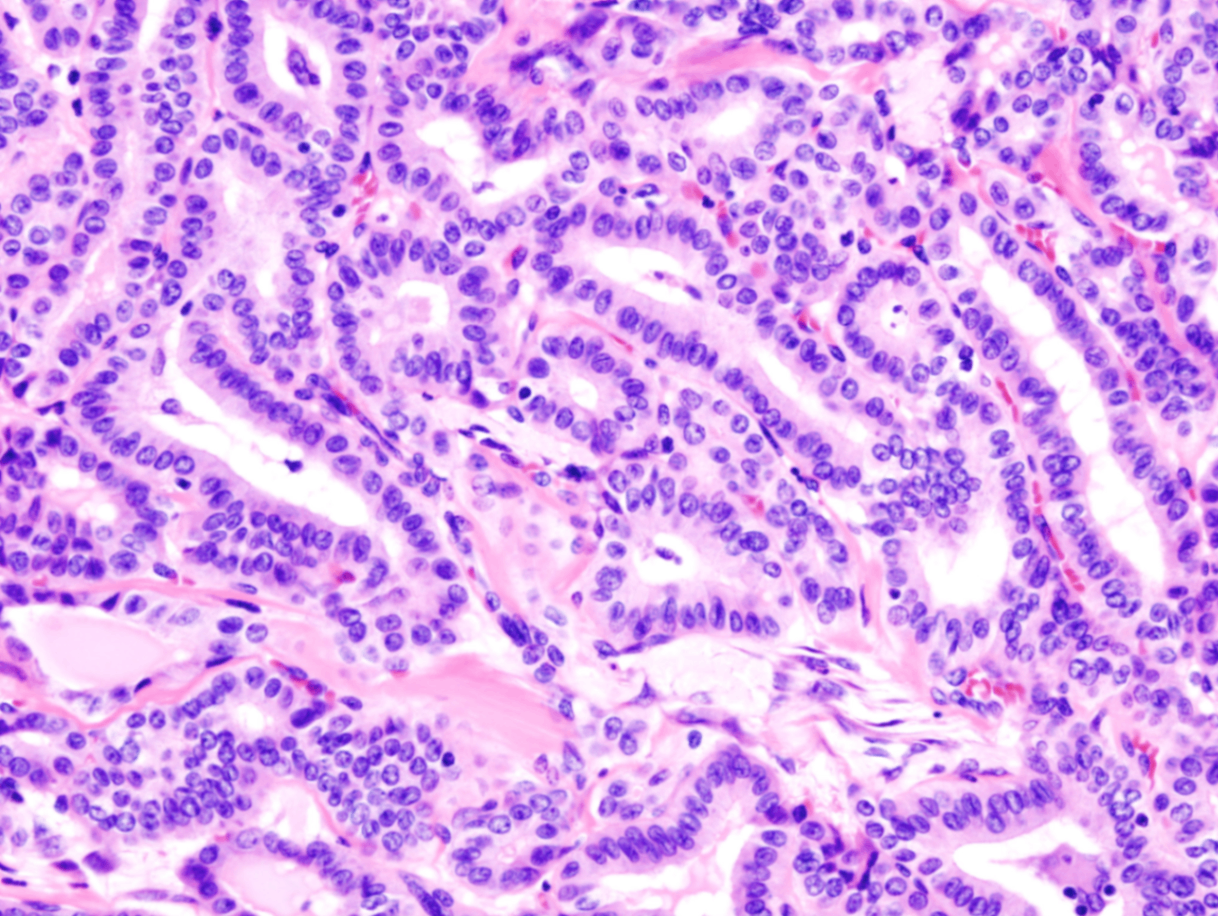

(2) 조직학적 소견

중심에 fibrovascular core를 가지는 분지된 유두구조; 유두를 덮는 상피는 대게 입방형 세포(cuboidal cells)

• 특징적인 핵 소견으로는 미세하게 분산된 염색질과 투명하거나 비어있는 핵 → 일명 "ground-glass nuclei", "Orphan Annie eye inclusion"

• 핵막 내 함입 (nuclear pseudoinclusion) 또는 핵 고랑 (nuclear grooves) 관찰 가능

• 동심성 석회화 구조인 psammomma bodies 또한 특징적으로 관찰됨

Papillary thyroid carcinoma histopathology, Wikipedia Commons